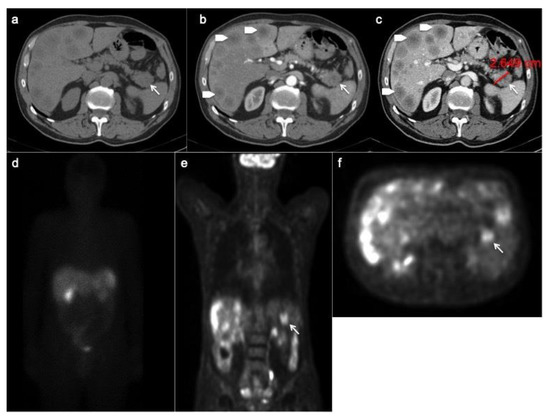

PET/CT with 68-Gallio labeled SSA is the imaging method of choice for panNEN functional study. There are mainly three available SSAs showing no substantial differences in patients staging: 68-Ga-DOTANOC, 68-Ga-DOTATOC (Figure 5) and 68-Ga-DOTATATE. All of them are SSRT2 high-affinity tracers; only 68-Ga-DOTANOC proved to have an affinity for SSRT3.

Figure 5.

CT images (a–c) show a hyper-enhancing pancreatic nodule in the body/tail of the organ (arrows) well depicted on the coronal (d) and sagittal (e) reconstruction too. The 68-Ga-DOTATOC PET/CT (f) shows focal uptake in the pancreatic lesion.